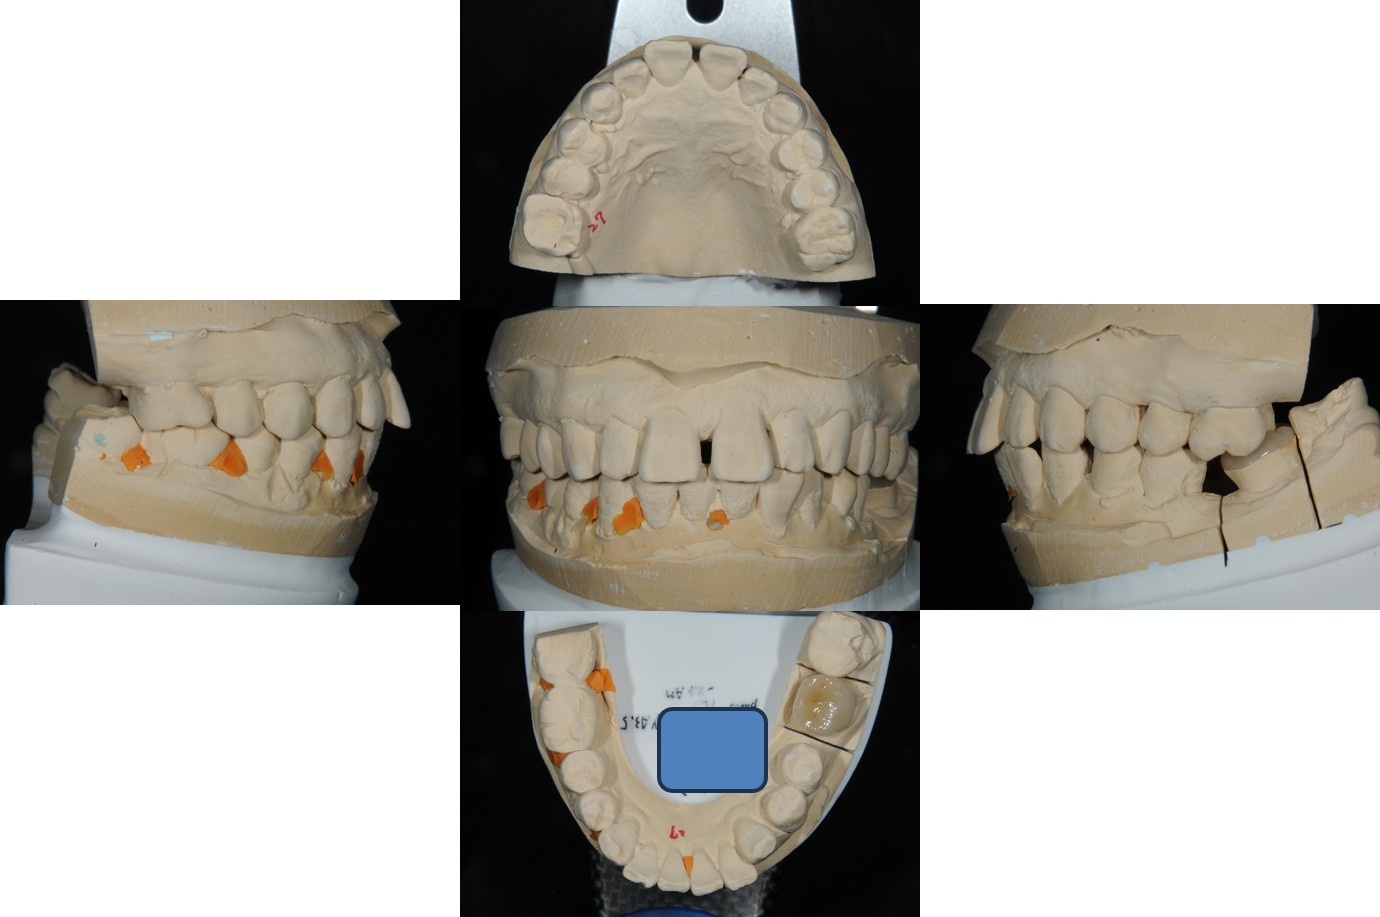

上咬合器

陶瓷冠蓋體製作

陶瓷冠塊體